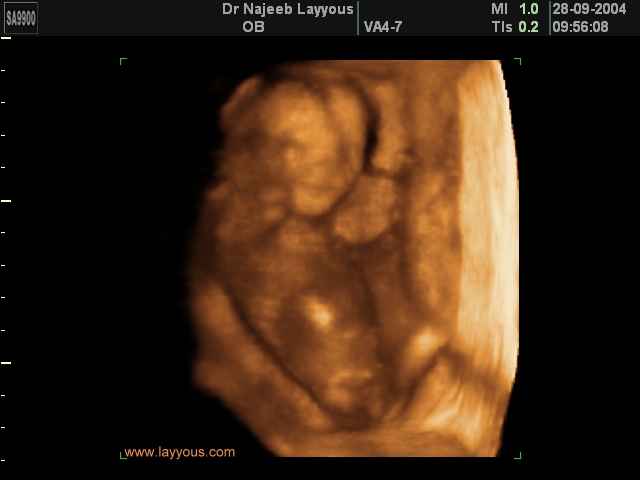

صور لتصرفات الجنين داخل الرحم بجهاز الالتراساوند ثلاثي الأبعاد | الدكتور نجيب ليوس

صور بجهاز الموجات فوق صوتية ثلاثي الأبعاد لتصرفات الجنين داخل الرحم